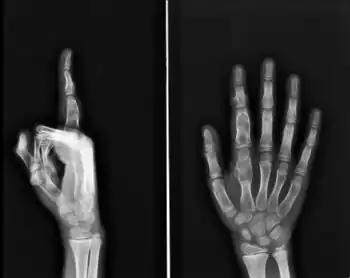

Multiple (enchondromatosis) in fingers